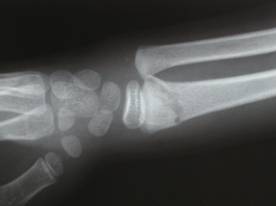

9歳 男性 右前腕骨骨折

学校で遊んでいてブランコから落ち、転倒した際手をつき負傷。

整復と針金副子固定を施し、手技療法により約三週間で治癒しました。